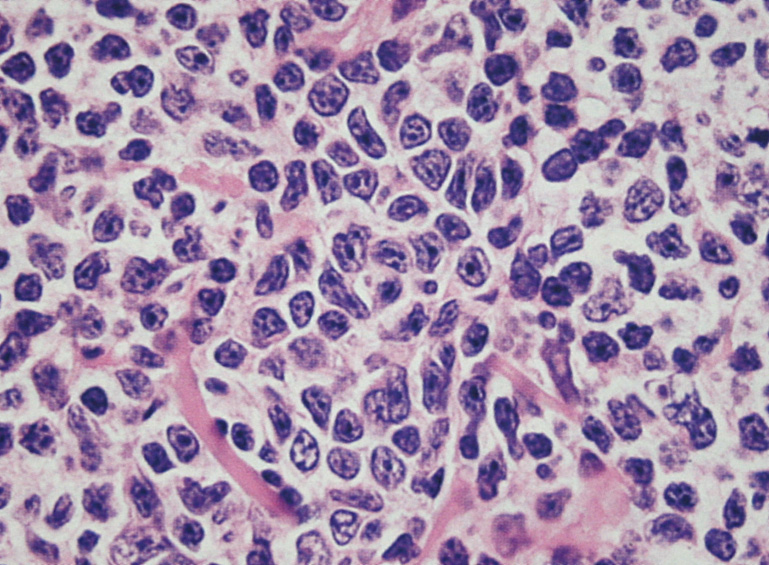

- 分化してplasma cell様の形態をとる. Dutcher body(核内偽封入体)など異型所見あり。

| centrocyte-like cell | monocytoid cell | plasmacytoid |